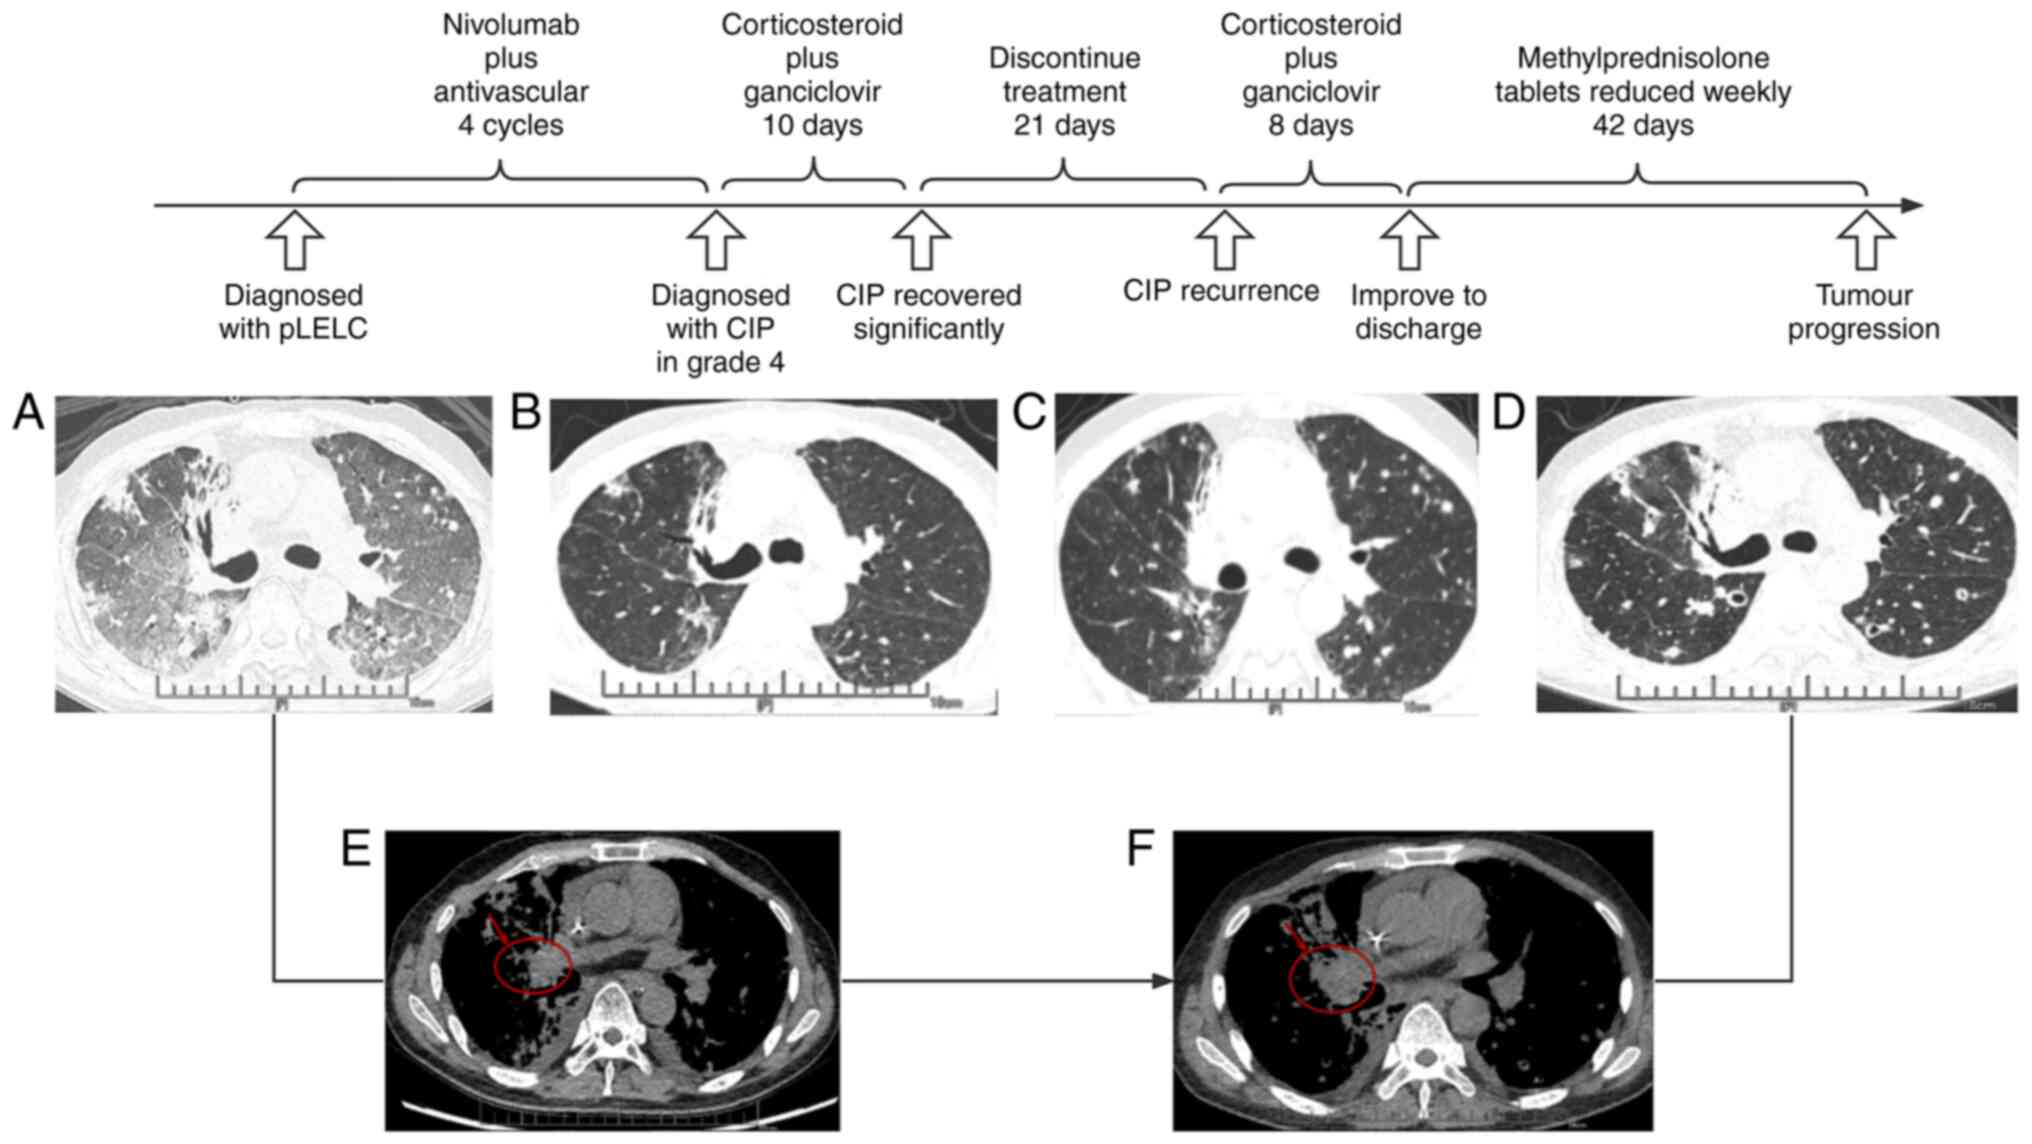

Figure 1

Timeline and CT manifestation. (A) Chest imaging at initial CIP diagnosis. (B) CIP imaging post-treatment with significant recovery. (C) Recurrent CIP images. (D) Routine tumor follow-up, indicating obvious enlargement (scale bars in cm). (E and F) Mediastinal window of the chest imaging at (E) CIP occurrence on first presentation of the patient and (F) follow-up visit (the arrow pointing to the circled area indicates the change of the tumor). CIP, checkpoint inhibitor-associated pneumonitis.

Following the third course of chemoimmunotherapy, in April 2021, the patient was immediately transferred to the First Affiliated Hospital of Guangzhou Medical University after one month of shortness of breath, which had become aggravated during the preceding three days. The patient presented with cough with expectoration, dyspnea, persistent pyrexia and a maximum body temperature of 40.5˚C. CT indicated a right middle lung tumor measuring ~2.3x1.8 cm, with interstitial inflammation in both lungs (Fig. 1) and involvement of the whole lung. It had been six months since the last radiotherapy and imaging did not indicate any shadows or streak-like changes consistent with the irradiated field or area, and radiation pneumonitis was thus excluded.

Laboratory tests revealed a concomitant gram-positive coccus infection. Based on medication history, clinical presentation and imaging, the diagnosis of severe CIP at the highest grade (IV) with concomitant pulmonary infection was considered. The patient was in a critical, life-threatening condition with plasma EBV 5.68x104 copies/ml as determined by fluorometric PCR at the pathology department (Fig. 2). Noninvasive assisted ventilation was quickly initiated combined with conventional intravenous corticosteroids 80 mg for anti-inflammation and meropenem for anti-infection, with simultaneous ganciclovir antiviral therapy for EBV. Following this, EBV dropped to 2.98x103 copies/ml on follow-up during antiviral treatment and corticosteroid was reduced to 40 mg intravenously (Fig. 2). Of note, the patient improved significantly within 10 days, at which time CT indicated that inflammation in both lungs was significantly reduced and other clinical signs were significantly improved (Fig. 1). The patient was discharged with only methylprednisolone tablets, despite final EBV 1.48x104 copies/ml, exceeding the normal level (5x102 copies/ml) (Fig. 2).

After three weeks, the patient returned with shortness of breath and cough with a small amount of white mucous sputum. Chest CT indicated no significant tumor changes and both lungs contained ground glass opacities (Fig. 1). Laboratory examination suggested no other pulmonary infection. Medical history review revealed that the patient had stopped corticosteroids without authorization after discharge and it was determined that the CIP had recurred. At this point, EBV had returned to a high level (1.14x105 copies/ml) (Fig. 2). The patient was treated with a conventional protocol of corticosteroid 40 mg combined with antiviral ganciclovir 0.25 g. The patient was stable eight days later, when he was administered chemotherapy combined with anti-vascular therapy to control the tumor, without immunotherapy rechallenge.

The patient returned to the hospital every three weeks for regular antineoplastic treatment. CT review six weeks after resumption of antineoplastic treatment revealed that the right lung tumor (4.5x3.1 cm) and lymph node metastases had all increased in size. In order to better display the changes, the mediastinal window on chest imaging is also provided (Fig. 1).